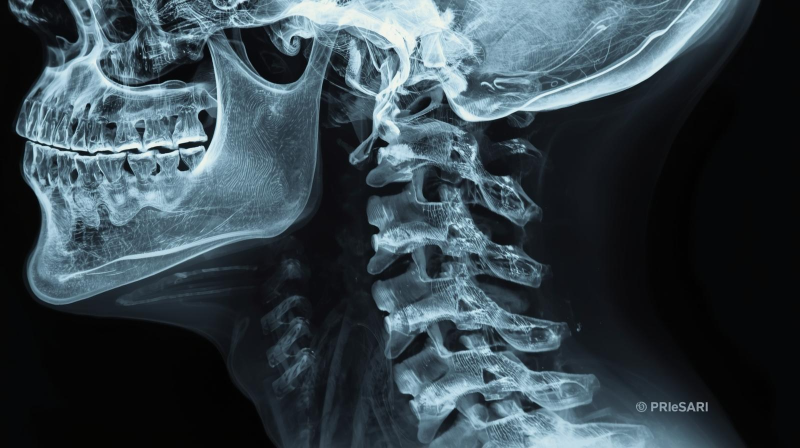

👉 이미 진행된 단계일 수 있으므로 X-ray, MRI 검사로 정밀 진단 필요

2. 목뼈와 그 변형의 이해

(1) 정상 목뼈

- 측면에서 보았을 때 C자 곡선이 자연스러운 상태

- 충격 흡수 및 균형 유지

(2) 일자목 (Straight Neck)

- C자 곡선이 사라지고 일자로 펴진 상태